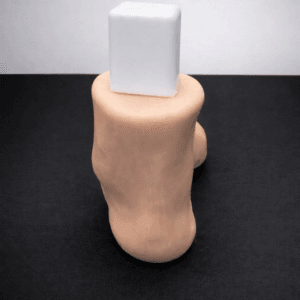

| Pathology | Pes Cavus |

| Area | Midfoot |

| Modularity | Single-piece |

| Material | Opaque |

Pes Cavus – Bone Model